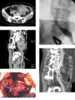

Compression of iliac vein

In human anatomy, the common iliac veins are formed by the external iliac veins and internal iliac veins. The left and right common iliac veins come together in the abdomen at the level of the fifth lumbar vertebra, forming the inferior vena cava. [Source: Wikipedia ]